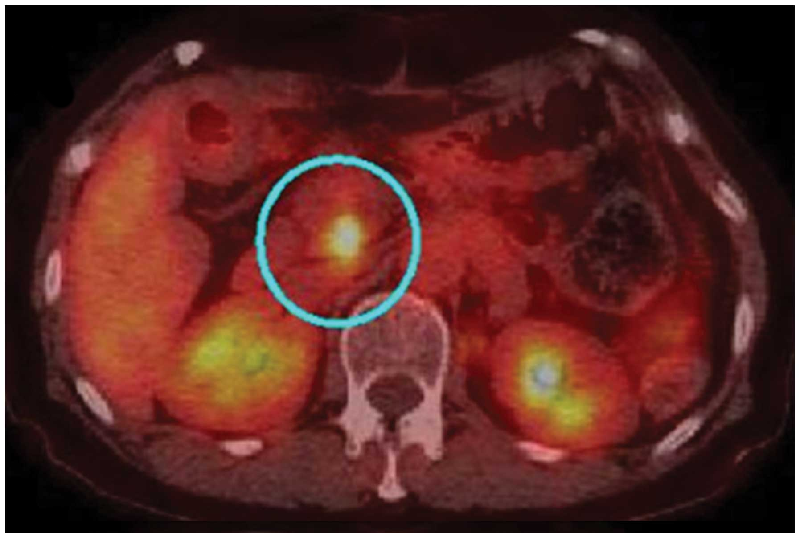

Как и другие опухоли, эта опухоль рака поджелудочной железы, показанная на ПЭТ-сканировании, может подвергаться возрастающему давлению со всех сторон по мере ее роста. Эксперименты показывают, что такое сжатие повышает лекарственную устойчивость.